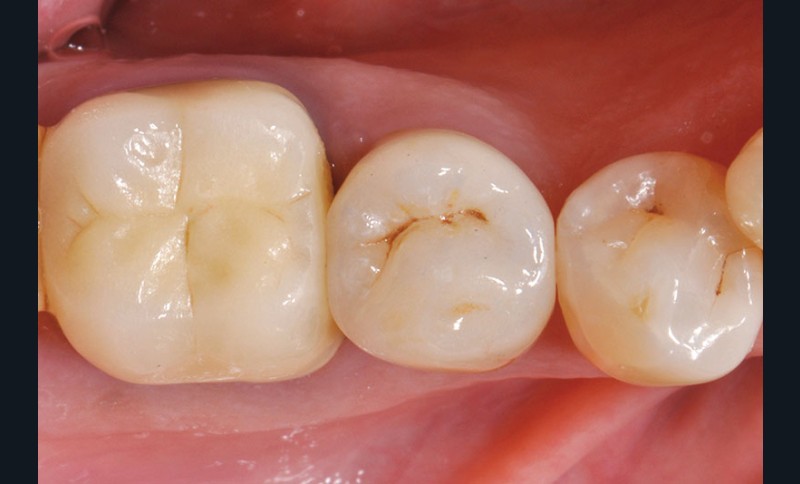

34, 35. Vues vestibulaire et occlusale de la prothèse d’usage collée sur 45 (Laboratoire du Sud-Ouest).